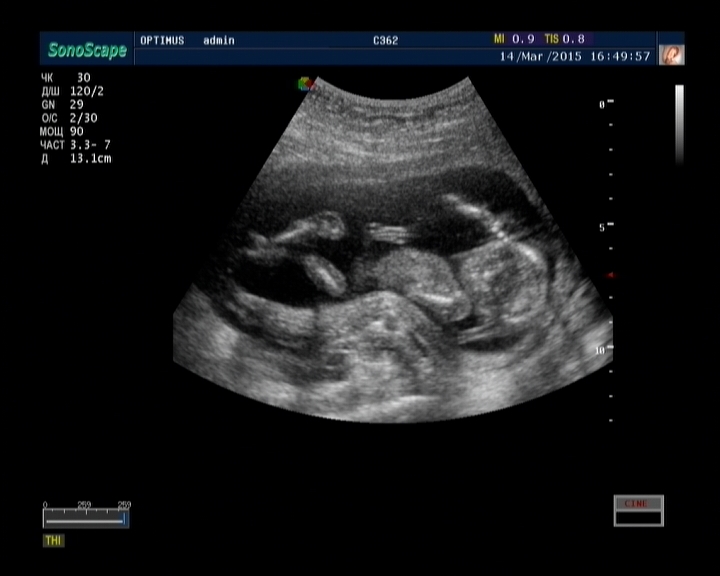

Только что вернулась со скрининга. Нахожусь под огромным впечатлением до сих пор! -)) Малявочка мой уже настоящий человечек!! Хотя животика у меня еще нет, а он там весь такой важный, лежит на спинке, ручками шевелит -))))

Не знаю, видимо я не представляла себе, что так четко его увижу, не особо об этом думала.. а тут такое! Я поражена! -)

Во второй скрининг наверное уже не так будет, там уже и животик будет, и шевелюшки, в общем уже и без узи, наверное, беременной себя ощущать буду -) А тут я даже переживала немного, что меня с узи выгонят, спросят зачем вапще пришла и долго ли буду из себя беременную строить -))) А там взаправду человечек лежит!!!! -)))) Вообще невероятно!